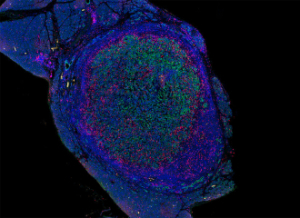

接受治疗后胰腺肿瘤中的T细胞(粉色)浸润了肿瘤细胞(绿色)图片来源:原文